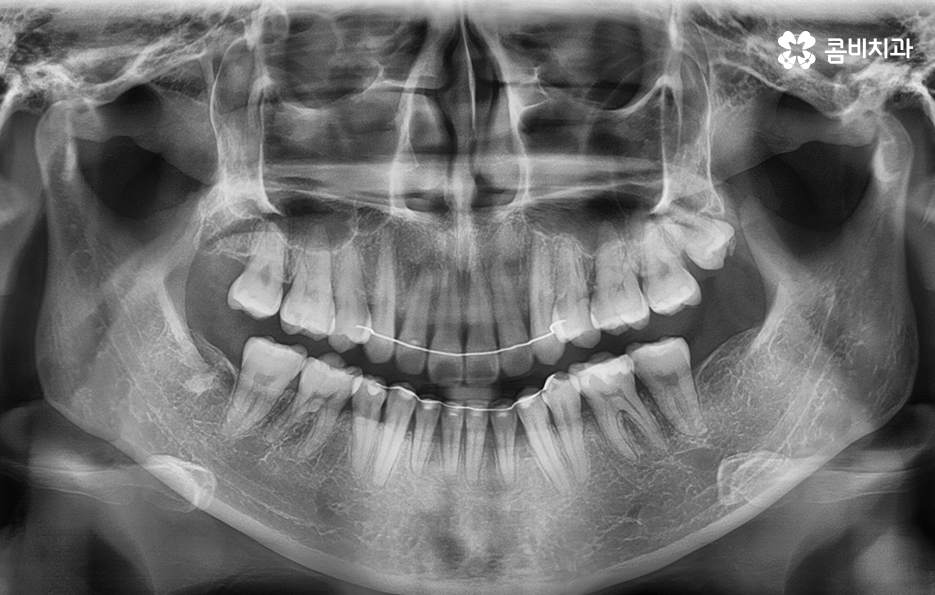

위 엑스레이 사진을 보시면 파란 원을 그린 부분이

발치를 한 부위이며 교정 기간이 경과함에 따라서

이 공간이 점점 메워지게 되고

가지런한 치열은 물론 돌출입도 개선됩니다.